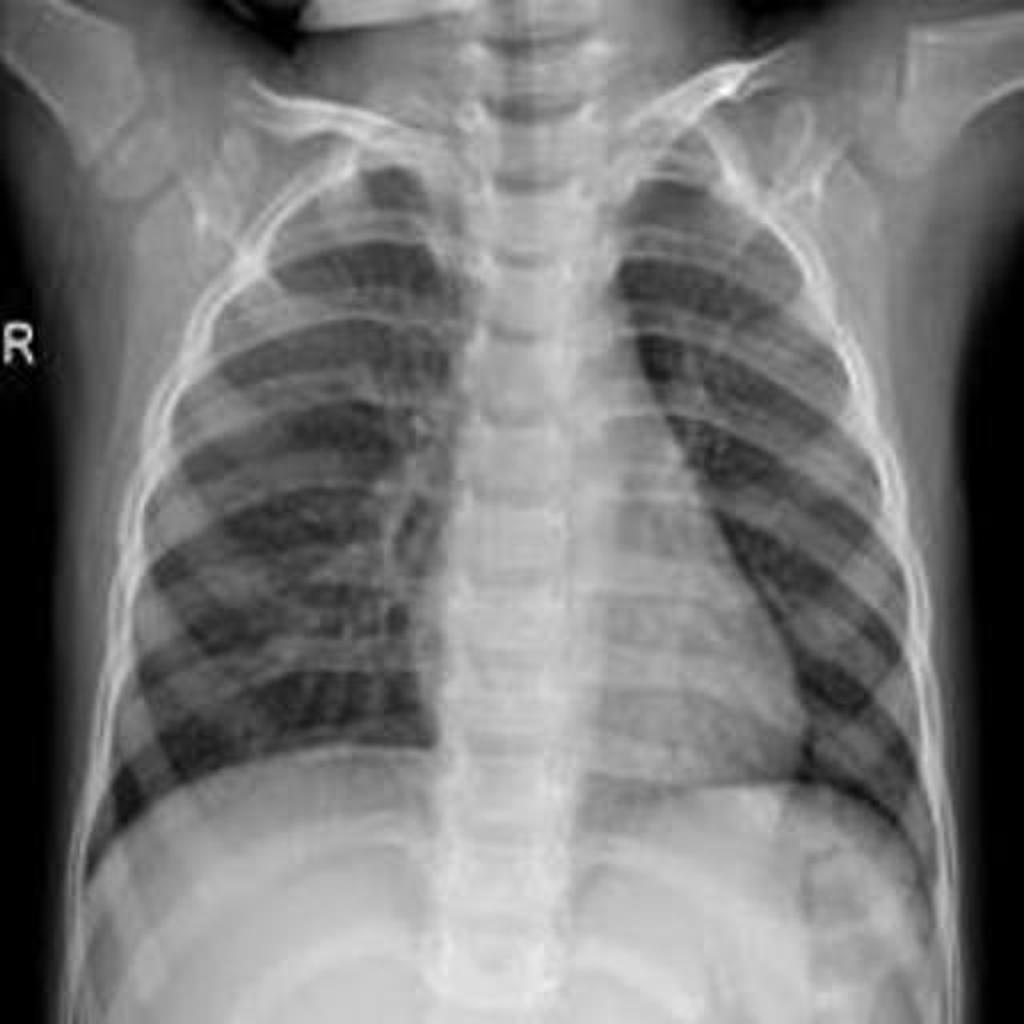

Göğüs röntgen (X-Ray)

cihazlarından alınan görüntüler kullanılarak derin öğrenme ve görüntü işleme tabanlı bir model oluşturulmuştur. Tasarlanan bu eğitilmiş model sayesinde COVID-19 sınıflandırılması geliştirilen web tabanlı yazılım prototiplemesi ile yapılabilmektedir.